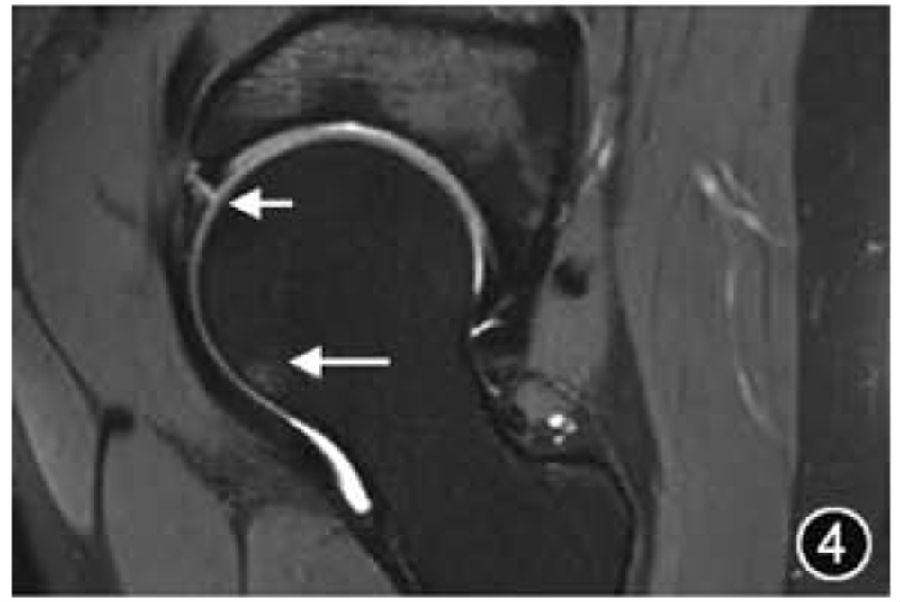

髋关节是由股骨头和髋臼组成的球窝关节,除中央凹外,股骨头周围有透明软骨覆盖,延伸至股骨头颈交界处。髋臼侧关节面呈新月形,关节软骨覆盖其前、上和后部区域,骨盆及股骨近端是红骨髓的储备部位,因此骨盆及股骨近端的骨髓信号通常不均匀(图1)。

图1 正常髋臼盂唇MRI图像。冠状面T2WI可清晰显示关节囊(↑)及盂唇软骨移行部(*)